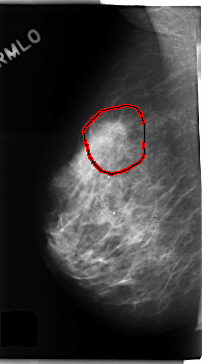

C_0194_1.RIGHT_MLO

RIGHT_MLO LINES 4728 PIXELS_PER_LINE 2624 BITS_PER_PIXEL 12 RESOLUTION 50 OVERLAY

FILE: C_0194_1.RIGHT_MLO.OVERLAY

TOTAL_ABNORMALITIES 1

ABNORMALITY 1

LESION_TYPE CALCIFICATION TYPE AMORPHOUS DISTRIBUTION CLUSTERED

LESION_TYPE MASS SHAPE IRREGULAR MARGINS SPICULATED

ASSESSMENT 5

SUBTLETY 5

PATHOLOGY MALIGNANT

TOTAL_OUTLINES 1

BOUNDARY